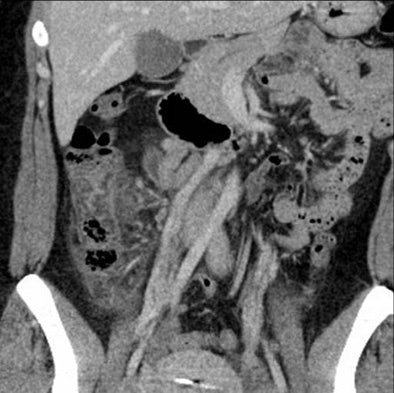

![]() |

| Above, appendicitis diagnosed with both oral and IV contrast. Below, another patient with appendicitis diagnosed with IV contrast alone, both with surgical confirmation. |

For the clinical diagnosis of diverticulitis, CT yielded a sensitivity and specificity of 91% and 99%, respectively, in the oral and IV contrast group (11 patients), and sensitivity and specificity of 90% and 97%, respectively, in the group that received only IV contrast (10 patients).